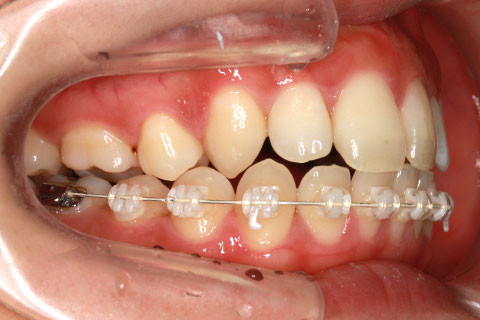

ハーフリンガル矯正3:上の歯のみ舌側矯正で治療(矯正期間24ヶ月)

治療前

治療中(開始直後)

治療中(開始半年後)

治療後

- 年齢・性別

- 25歳女性

- 治療期間

- 2年0ヶ月

- 抜歯

- 上下4番抜歯

- 治療費

- 110万円

- 備考

- 治療内容

- 施術の副作用(リスク)

- 表側矯正と比較して、力学的な操作性が複雑なため、ボーイングエフェクトを起こしやすい。